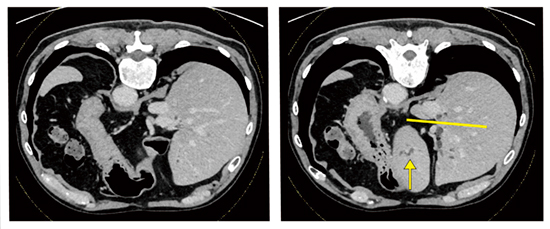

●症例3:遠位胆道がん(70歳代、男性)

本症例は結節型腫瘍があり、上流側の拡張が見られた(図5)。膵頭十二指腸切除術は必要であると考えられ、上流側の進展範囲診断目的にERCPを施行した。

図5 症例3:遠位胆道がん(70歳代、男性)